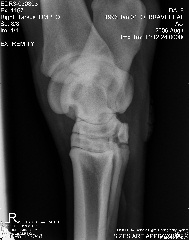

Here are the xrays from today:

Stifle oblique:

Stifle Oblique

Aileen, carefully reviewing an extensive list of radiographs like you have above for any abnormality even with the original set of full sized radiographs could take up to an hour and an hour more to write about. Reviewing these tiny pictures would be of no value at all. While I don't mind looking at the occasional radiograph the above is beyond the scope of this site.

If you want a second opinion on these I strongly recommend you send them to a certified veterinary radiologist, like you find at a university veterinary school, they could tell you more than I would be able to.

Surgeon says mild to moderate djd in hocks and stifle. His stiffness is much much better, not overall anymore, so I do think the hock injections helped.